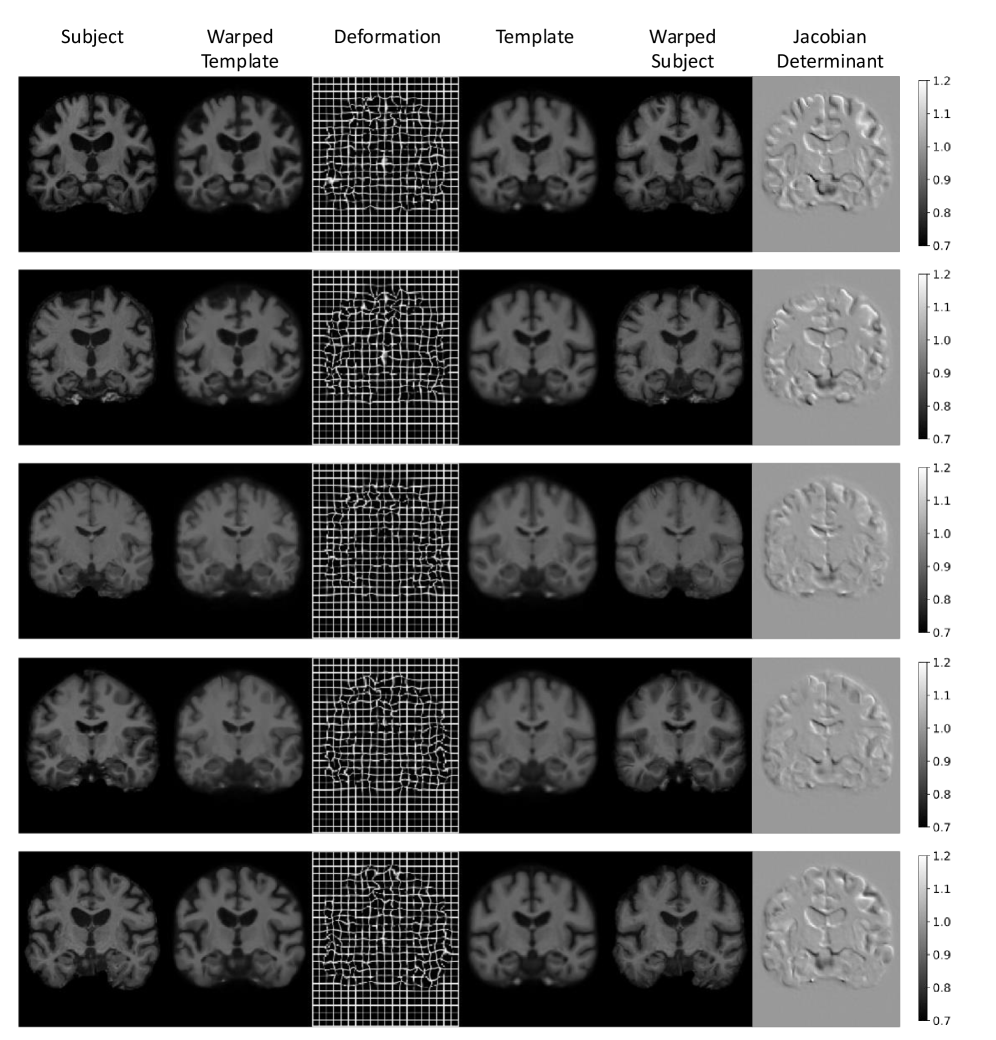

Figure 10 shows example predictions produced by AtlasMorph and their corresponding deformation fields and Jacobian determinants. The values of the Jacobian determinant are close to 1, which indicates small deformation norms.